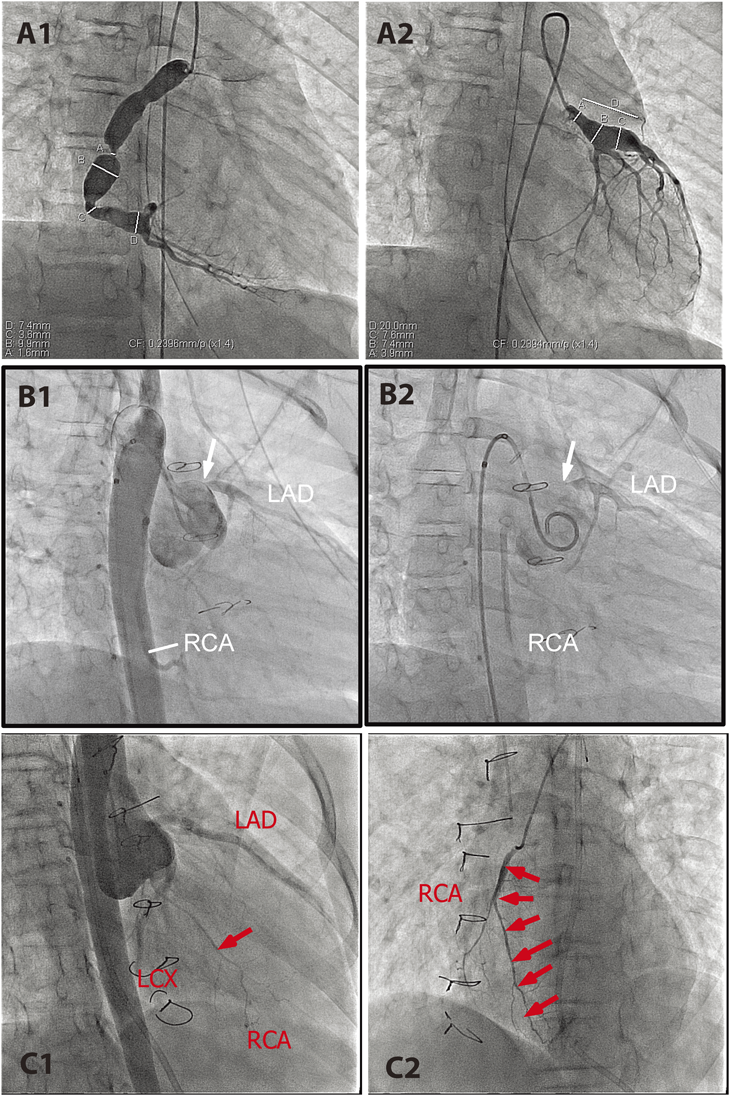

Fig. 1 Congenital coronary anomalies in children. A1 and A2: Coronary angiograms of 3-month-old male infant with anomalous left coronary artery from pulmonary artery (ALCAPA) who presented with irritability, respiratory distress, paleness, and feeding difficulty. Aortic root injection revealed only right coronary artery (RCA) arising from aorta (A1). Selective right coronary angiogram filled left anterior descending artery (LAD) and left circumflex artery (LCX) retrograde via collateral vessels (arrows). B: CT coronary angiogram of 19 years old asymptomatic male with anomalous aortic origin of coronary artery (AAOCA). Left coronary artery arises from the right coronary cusp and runs between the great vessels (arrows). C1 and C2: Aortic root injection before (C1) and after (C2) the deployment of a vascular occlusion device (a white arrow in C2) in the dilated coronary arterial fistula (CAF; arrows) from RCA to right atrium (*) in asymptomatic 3 years old boy who was diagnosed at 2 months of age because of continuous murmur. D1 and D2: A 4-day-old full term male infant with pulmonary atresia with intact ventricular septum and RV-dependent coronary circulation (RVDCC). D1: RV injection shows sinusoidal vessels communicating to native coronary artery system. D2: Aortic root injection reveals mild proximal narrowing of left coronary artery (LCA: arrow), suggestive of RVDCC

Anomalous left coronary artery from pulmonary artery (ALCAPA) is a rare congenital coronary anomaly typically presenting in infants around 2 to 3 months of age with acute onset of respiratory distress, poor feeding, and paleness secondary to circulatory failure.8–10) These clinical manifestations are attributed to myocardial infarction due to direct myocardial ischemic injury and associated left ventricular (LV) dysfunction and mitral regurgitation (MR). Early diagnosis and prompt surgical intervention (coronary translocation surgery) are essential for the better prognosis (Fig. 1A1, A2). Some infants completely recover LV function after an early diagnosis and a prompt surgical intervention.11–14) It is surprising that infantile myocardium regenerate, even after extensive myocardial damage.15)

Patients with ALCAPA can be totally asymptomatic during childhood. There may be a mild cardiomegaly secondly to the increased left to right shunt with no clinical signs of myocardial ischemia or congestive heart failure. These patients are often encountered in adulthood with difficulty breathing, exercise intolerance, palpitation, chest pain, syncope,16–18) or even SCD.19) Associated late mitral valve insufficiency may complicate a clinical picture of chronic ischemic cardiomyopathy after initial surgical repair in early childhood.12, 20) Diversity of clinical presentation of ALCAPA is thought to depend on the degree of collateral vessel development, the extent of irreversible myocardial ischemic injury and fibrosis, associated hemodynamic abnormalities (pulmonary hypertension,21) large ventricular septal defect,22) patent ductus arteriosus,23) or severe branch pulmonary stenosis24)), and increased myocardial oxygen demand from LV dilatation. ALCAPA includes a clinical spectrum of significant spatiotemporal heterogeneity of myocardial ischemia due to congenital coronary anomaly.

Aberrant aortic origin of coronary artery (AAOCA), another rare congenital coronary anomaly, occurs when the coronary artery arises from the different aortic cusps, consisting of left coronary artery (LCA) from the right aortic cusp and right coronary artery (RCA) from the left aortic cusp. This anomaly is frequently associated with other anatomical abnormalities including interarterial course, intramural course, a slit-like coronary orifice, and an acute angle from the aorta, which are speculated to be the underlying mechanisms of sudden disruption of coronary blood flow at the peak of exercise.25–27) The majority of patients with this condition remain asymptomatic, but the first symptom may be cardiac arrest or SCD, particularly aberrant aortic origin of left coronary artery (AAOLCA)28, 29) (Fig. 1B). AAOLCA is the second most common disease responsible for otherwise healthy young athletes during exercise (first is hypertrophic cardiomyopathy).30) The affected patients seldom experience ischemic chest pain or other warning signs of myocardial ischemia before the fatal event. AAOLCA is generally indicated for surgical intervention (coronary translocation or unroofing of intramural artery) because of a high association with SCD in otherwise healthy individuals.25) The surgical indication for aberrant aortic origin of right coronary artery (AAORCA) remains controversial.31)

Coronary Artery Fistula

Coronary artery fistula (CAF) or coronary cameral fistula implies fistulous communication between the existing coronary artery to any of the cardiac chambers (right atrium, left atrium, right ventricle, and left ventricle) or vessels (pulmonary artery)32, 33) (Fig. 1C1, C2). It can be small or enlarged with aneurismal morphology. Usually, CAF is diagnosed in asymptomatic patients with continuous murmur during childhood or clinical signs of left ventricular volume overload in adult patients. Adult patients may present with exercise intolerance or atrial arrhythmia due to volume overload and/or myocardial ischemia secondary to myocardial steal phenomenon.33) Echocardiography with a color Doppler study is usually sufficient to make a diagnosis. In children with asymptomatic CAF, fistula may be electively occluded with closure-device or coils under cardiac catheterization or surgically ligated. Symptomatic adult patients require necessary intervention. An understanding of correct coronary anatomy is crucial for intervention, as postoperative thromboembolic complications are reported.34–36)

Pulmonary Atresia with Intact Ventricular Septum

Variable coronary abnormalities are known to complicate in pulmonary atresia with intact ventricular septum (PA/IVS). Persistent exposure to significantly elevated right ventricular pressure predisposes the development of sinusoidal communication between the right ventricular cavity and existing coronary arteries (Fig. 1D1, D2).37) When this sinusoidal communication becomes predominant, the intrinsic coronary arteries may develop regression, causing proximal coronary stenosis or coronary atresia.38, 39) This condition is called “right ventricle-dependent coronary circulation (RVDCC),” and is responsible for an increased risk of myocardial ischemia or steal phenomenon with RV-decompression surgery or even shunt placement.40–42) This underlying coronary anomaly is responsible for high perioperative morbidity and mortality. It is essential to assess the possibility of RVDCC prior to surgical intervention to minimize the risk of myocardial infarction during and after surgery.43)